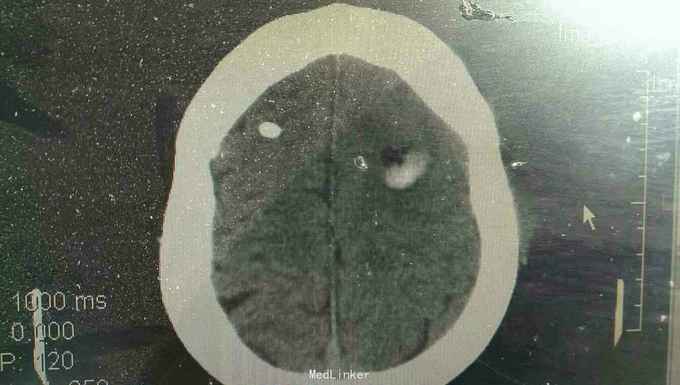

患者男性,56岁。以突发头痛伴意识不清半小时入院。患者入院半小时前突然自觉头痛,性质剧烈,呕吐多次,随即意识不清。来我院就诊。

浅昏迷状态,无语言。刺激后右侧肢体不动,左侧肢体可动。双侧瞳孔等大正圆,直径3.0毫米,光反射迟钝。右侧病理反射阳性。

脑出血,高血压病 急诊行微创硬通道内镜下血肿清除术,术中清除大部分血肿,患者术后第二天清醒右侧肢体三级,语言迟缓。